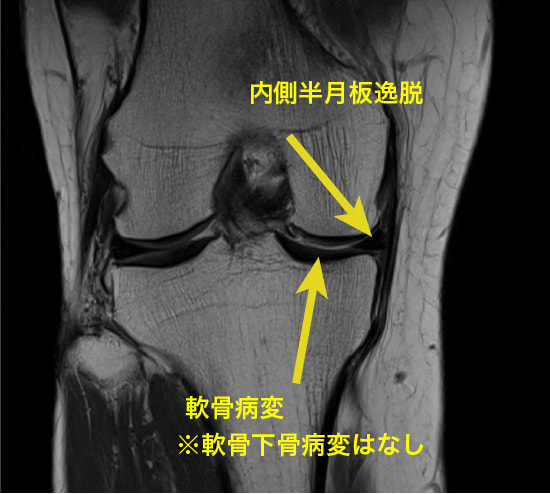

上記に紹介している膝のMRIは変形性膝関節症の原因の1つとして指摘されている、「内側半月板後根(後節)損傷MMPRT」の一症例です。

膝関節の方面のCOR画像(前額面)ですが、内側半月板の水平断裂が見られます。

症例:半月板の逸脱

半月板hoop機能(荷重ストレスの分散)の破綻が急激な変形性膝関節症の進行の一因とされています。

軸方向の機械的ストレスの約70%が半月板を介して分散されていることを考えれば、半月板の損傷や逸脱によって変形性膝関節症に発展することは想像ができるでしょう。

内側半月板の前角と後角は、関節包や靭帯と連続しつつ、骨へ強固に付着しています。この骨への付着部は、半月板が関節にかかる荷重を分散する際の固定点として機能し、適切な位置で半月板が荷重を受けることを可能にします。特に、内側半月板の後根部の付着は、関節の荷重負荷に対抗するための重要な要素です。

半膜様筋が関節包に付着し、その関節包の張力に関与しているため、内側半月板の逸脱に関してのターゲットは「膝関節のアライメント調整」と「半膜様筋の促通」です。